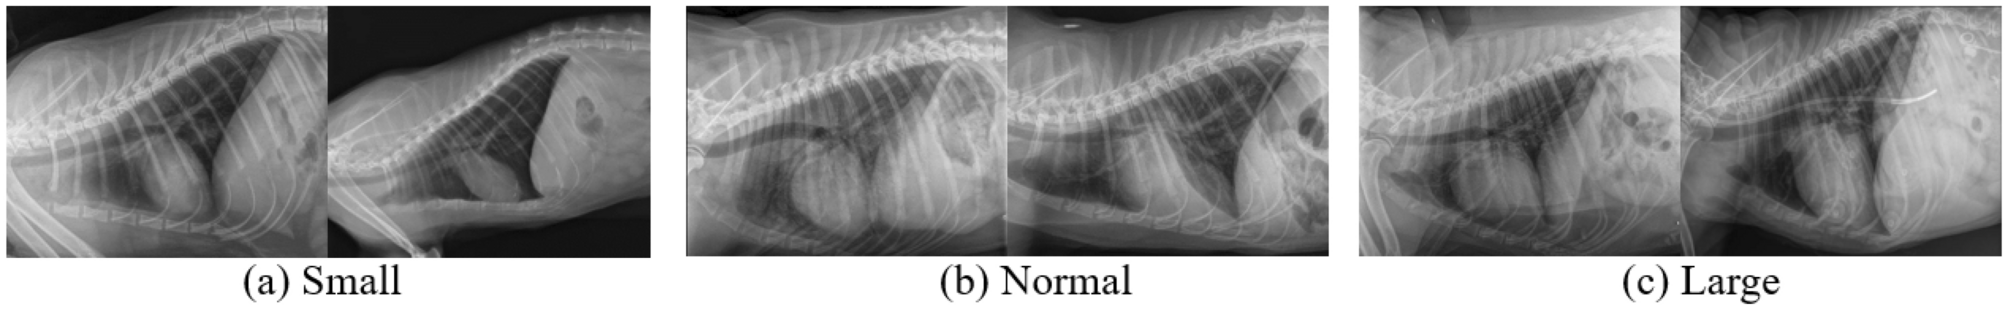

Six sample dog X-ray images of our collected DogHeart dataset.